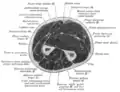

Click image to enlarge - ulnar nerve is visible in lower left